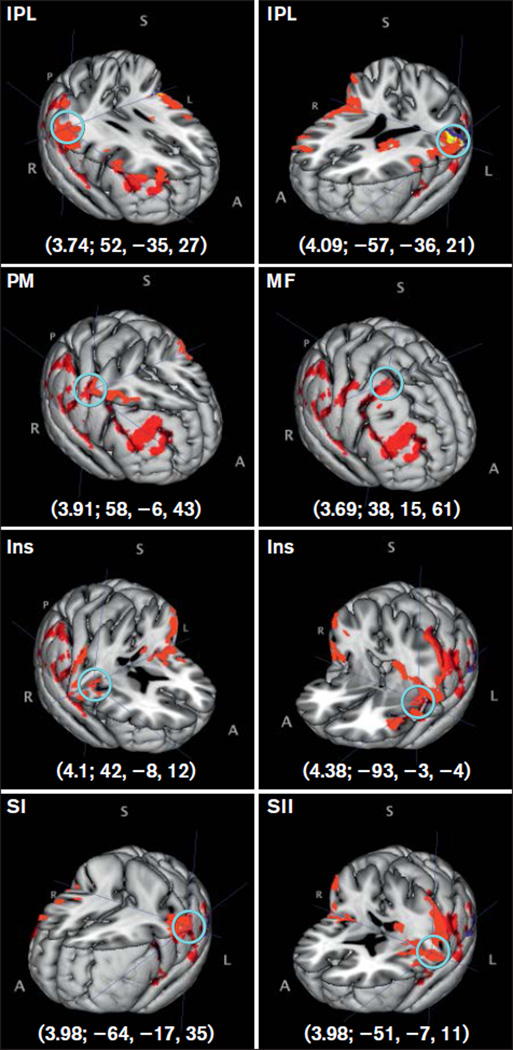

Fig 3.

Additional significant brain activations (a, left-sided; b, right-sided) found using a fixed-effects model. Middle column shows comparison between PDAP patients and controls under stimulus-intensity match condition with the brain area with peak activity noted, followed by its z-score and MNI coordinates (z-score; X, Y, Z). A light-blue circle shows the peak activity voxel corresponding to the reported z-score. PM = premotor cortex; Ins = insula, Thal = thalamus; Caud = Caudate nucleus. A = anterior; S = superior; I = inferior; P = posterior; R = right; L = left. Red = PDAP; green = controls stimulus-intensity match; blue = controls subjective-pain match; yellow = overlap.

No significant group differences were found when a mixed-effects model was used; unthresholded z scores from this analysis in the same MNI coordinates from the fixed-effects model results are shown in Table 4. Group mean activations using a mixed-effects model were found for PDAP patients and control subjects under the subjective-pain match condition (Table 5) but not for the stimulus-intensity match. Activations in the insula and IPL bilaterally, left SI, left SII, right premotor cortex, and right middle frontal gyrus were found for PDAP patients, while only the left IPL was found active for control subjects under the subjective-pain match condition (Fig 4).

Significant between-group brain activation differences between PDAP patients and control subjects in both match conditions were found using a fixed-effects model (Table 4). Under the stimulus-intensity match condition, PDAP patients had greater brain activation in several brain regions compared to control subjects. Two major activation clusters were seen and included regions related to the sensory-discriminative aspect of pain processing (primary [SI] and secondary [SII] somatosensory cortices) and somatosensory integrative cortical areas (inferior parietal lobule [IPL]) bilaterally (Fig 2). Other cortical areas of activation that may be involved in pain perception included the insula and premotor cortex bilaterally (Fig 3), right middle frontal gyrus, frontal orbital cortex, and superior parietal lobule; subcortical areas included the right thalamus, right cerebellum, and left caudate nucleus (Fig 3). Of interest, several areas showing significant differences between control subjects and PDAP patients under the stimulus-intensity match condition (SI, SII, IPL, premotor cortex, insula, thalamus) also displayed overlapping of group mean brain activations under the subjective-pain match condition (Figs 2 and 3, yellow-colored locations highlighted by light-blue circle). When matched to subjective pain ratings, PDAP patients also exhibited greater activation compared to control subjects although in a less extensive region, which included SII, premotor cortex, insula, inferior frontal gyrus, and middle frontal gyrus—all on the right side—and the left frontal orbital cortex (Table 4). Control subjects had no brain regions with significantly greater activation relative to PDAP patients under the stimulus intensity or subjective-pain match conditions.